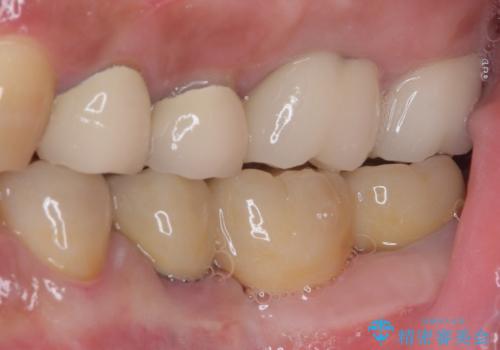

仮歯がない状態を極力避けたいとのことで、外科処置を少しずつ進めていくことになり、治療期間は2年間を要しました。

治療後は痛みなどなく、快適に噛めるようになりました。